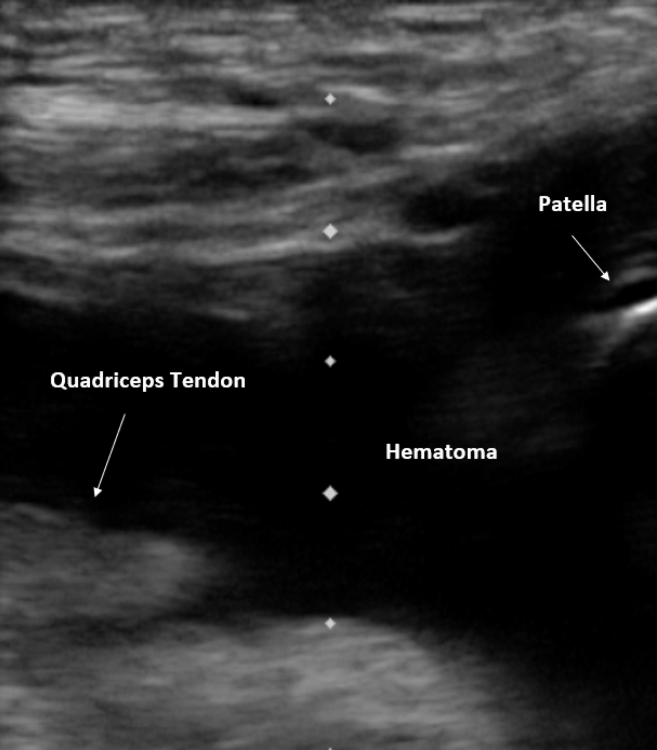

Abstract Image